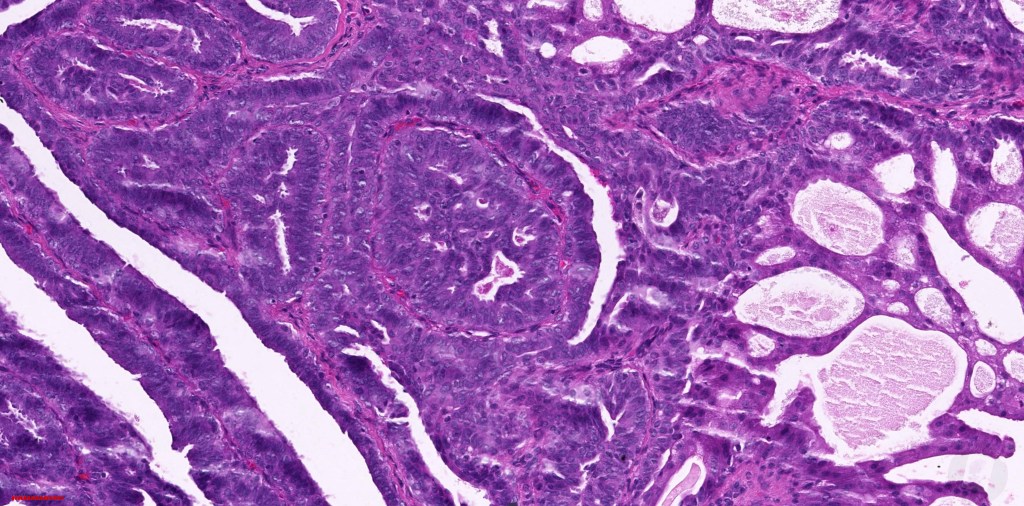

Histological features

•Cystic or solid

•Papillae lined by myoepithelial cells with overlying epithelial cells with eosinophilic cytoplasm showing decapitation secretion

•Cribriform pattern sometimes evident

•Solid pattern